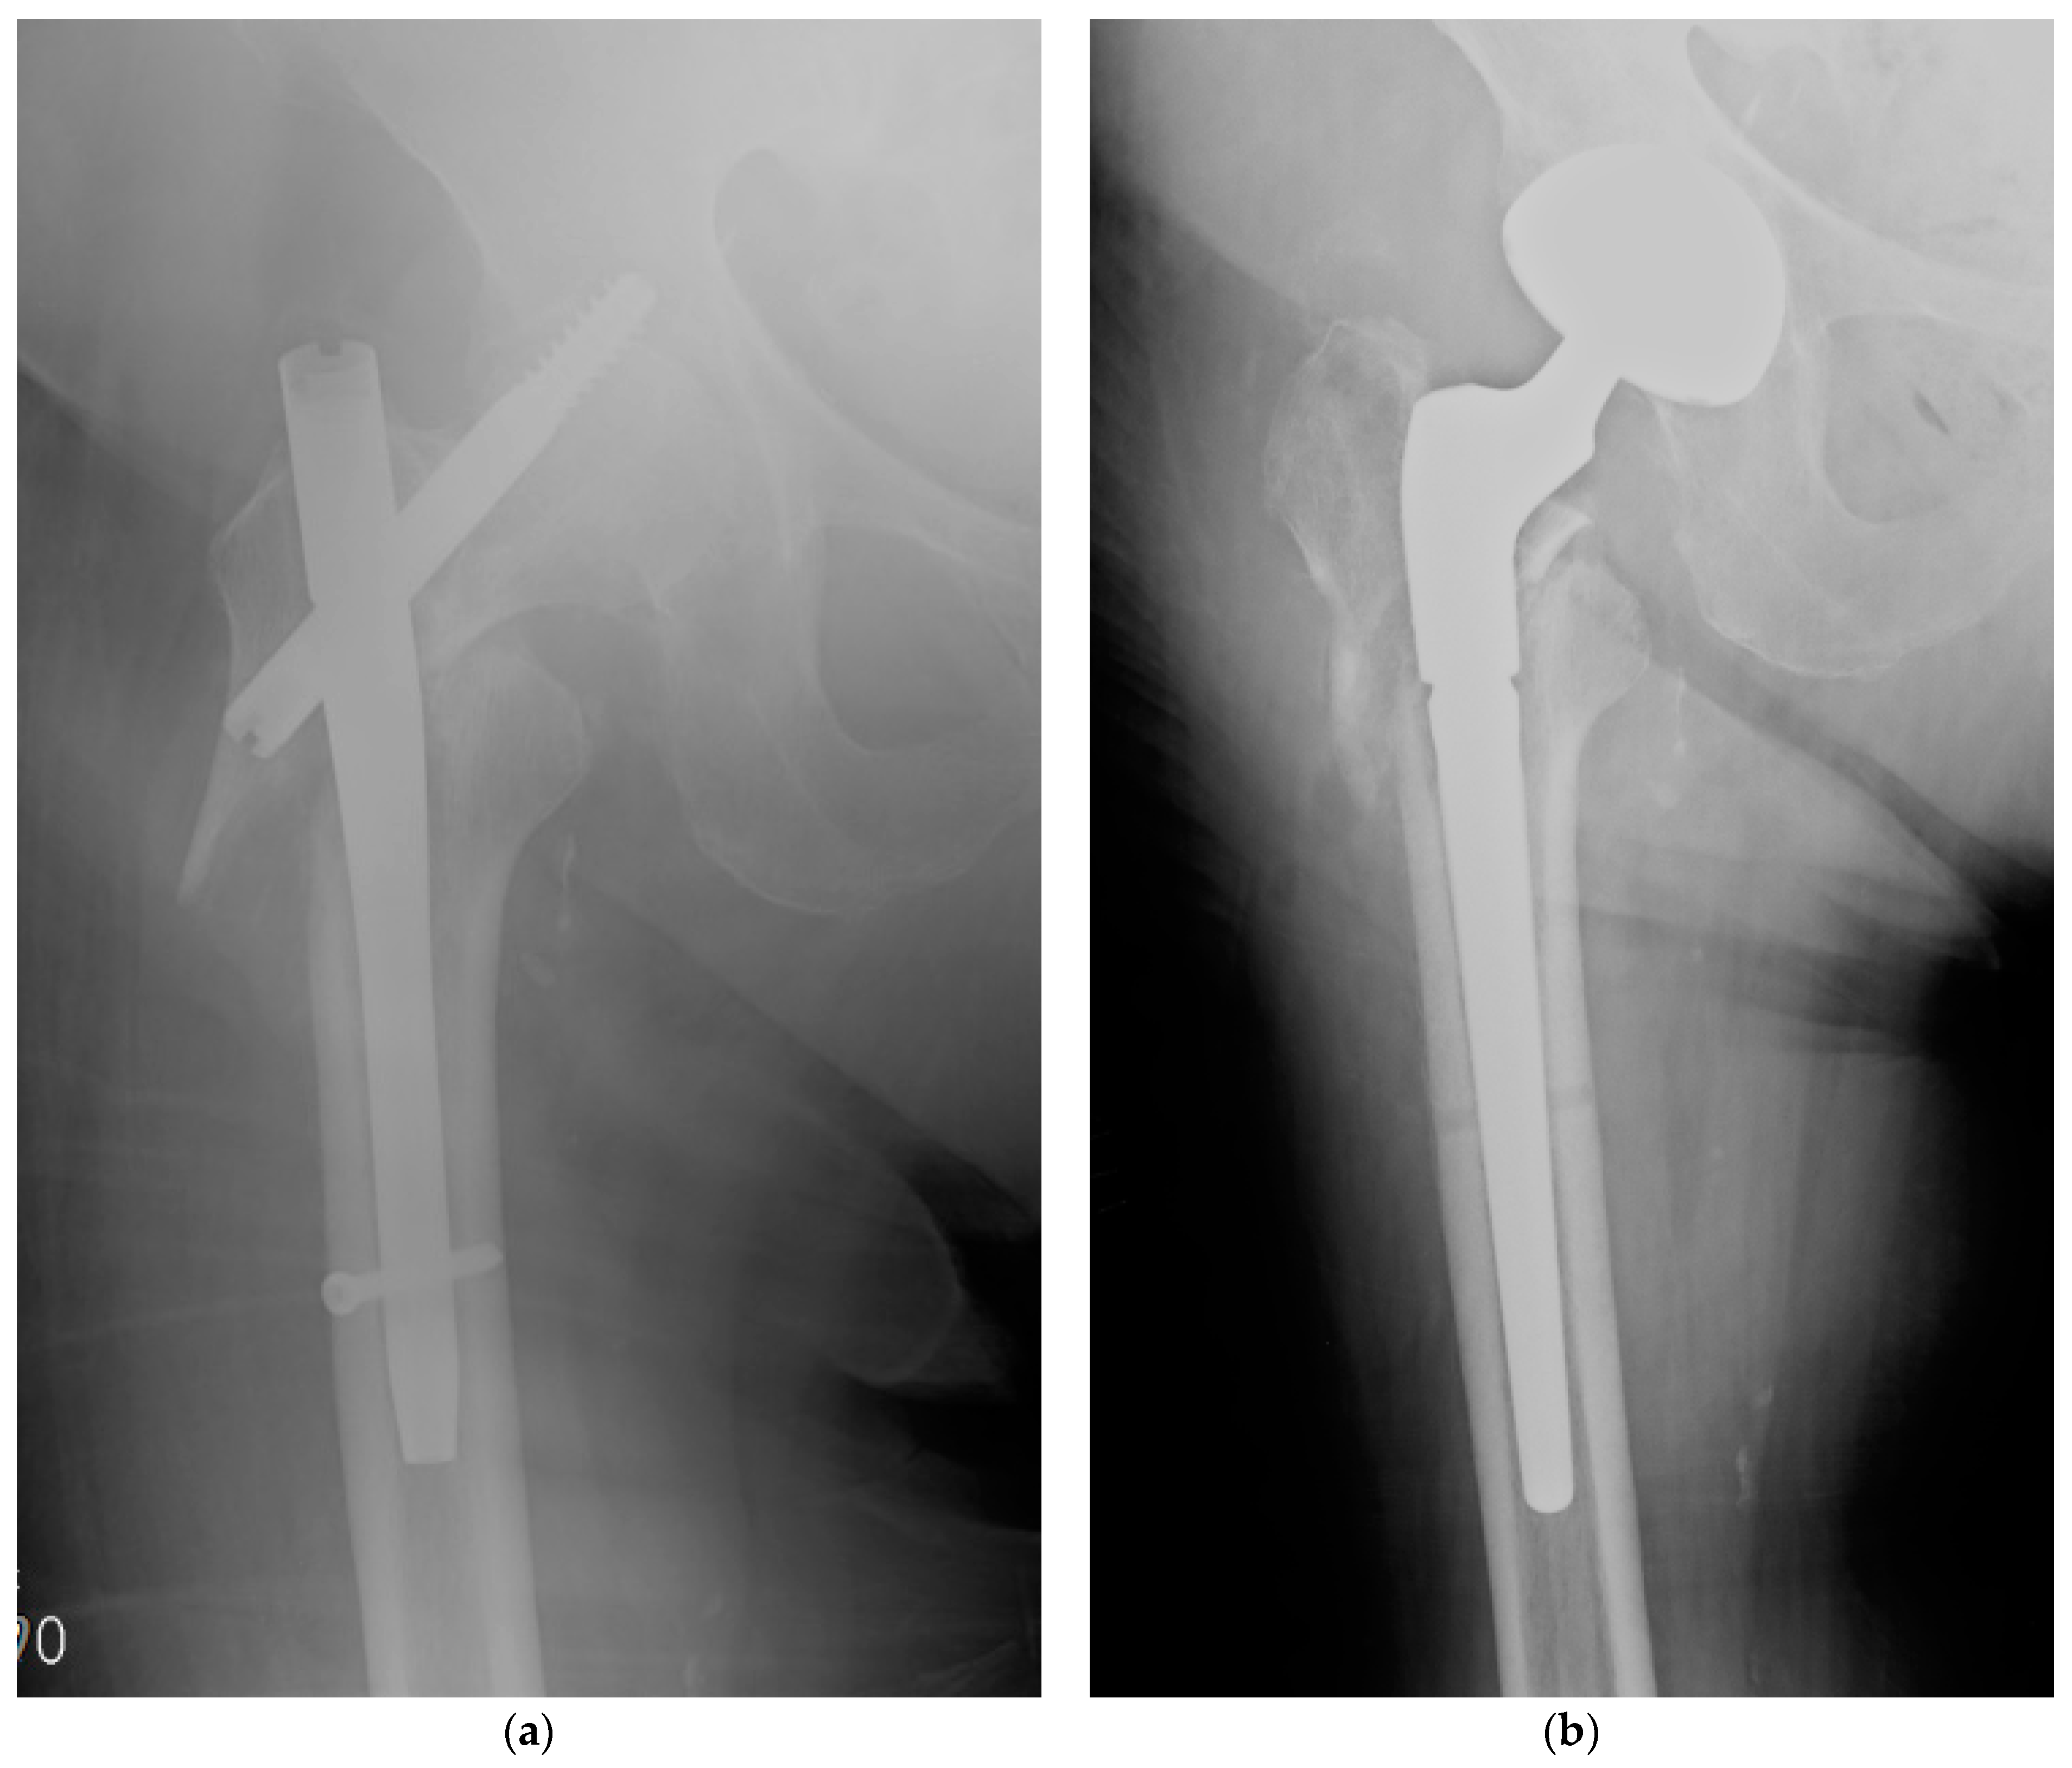

- De Meo, D.; Calogero, V.; Are, L.; Cavallo, A.U.; Persiani, P.; Villani, C. Antibiotic-Loaded Hydrogel Coating to Reduce Early Postsurgical Infections in Aseptic Hip Revision Surgery: A Retrospective, Matched Case-Control Study. Microorganisms 2020, 8, 571. [Google Scholar] [CrossRef] [PubMed] [Green Version]

- Zagra, L.; Gallazzi, E.; Romanò, D.; Scarponi, S.; Romanò, C. Two-stage cementless hip revision for peri-prosthetic infection with an antibacterial hydrogel coating: Results of a comparative series. Int. Orthop. 2019, 43, 111–115. [Google Scholar] [CrossRef]

- Capuano, N.; Logoluso, N.; Gallazzi, E.; Drago, L.; Romanò, C.L. One-stage exchange with antibacterial hydrogel coated implants provides similar results to two-stage revision, without the coating, for the treatment of peri-prosthetic infection. Knee Surg. Sports Traumatol. Arthrosc. 2018, 26, 3362–3367. [Google Scholar] [CrossRef]

- Pellegrini, A.; Legnani, C. High rate of infection eradication following cementless one-stage revision hip arthroplasty with an antibacterial hydrogel coating. Int. J. Artif. Organs 2021, in press. [Google Scholar] [CrossRef] [PubMed]